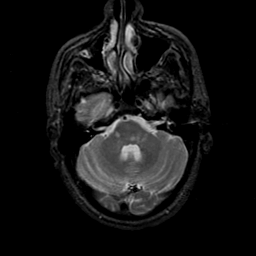

MR Study #23, January 26, 1992 -- Slice #12